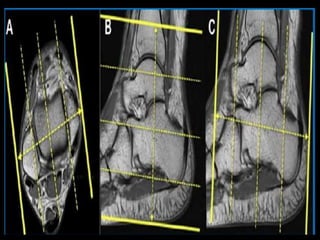

(a) Coronal T1 weighted image of the ankle demonstrates the tibiotalar joint (blue arrow) and

distal tibiofibular joint (red arrow). The osseous structures include the tibia (T), tibial plafond

(Tib Plaf), medial malleolus (MM), lateral malleolus (LM), talus (Tal), superior faces (SF), lateral

malleolar facet (LMF), medial malleolar facet (MMF), calcaneus (C), peroneal tubercle (PT), and

sustentaculum tali (ST). (b) Sagittal T2 weighted image again demonstrates the tibiotalar joint

(blue arrow), as well as the subtalar joint (yellow arrow). The talus to include the head (TH),

neck (TN), and body (TB) are noted, as well as the calcaneus (C).